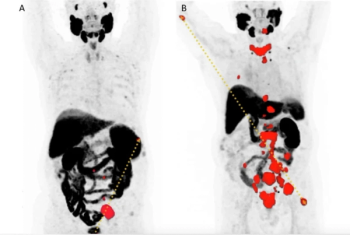

In patients with high-risk, hormone sensitive prostate cancer who had no evidence of metastasis on conventional imaging, PSMA PET revealed polymetastatic disease in 24 percent of patients and M1 disease staging in 46 percent of patients.